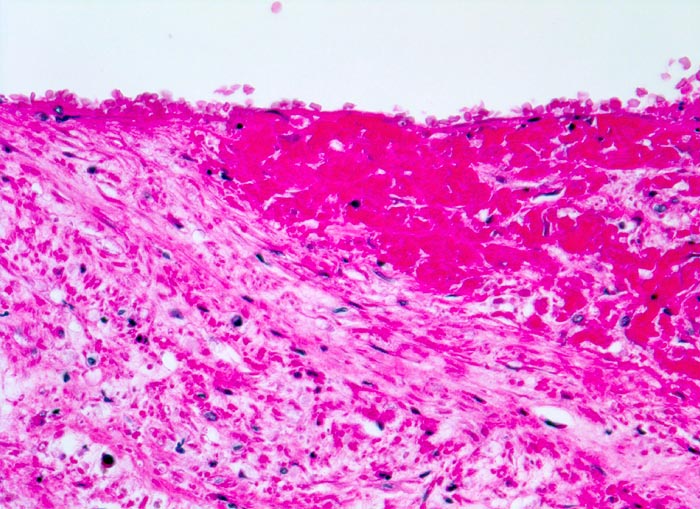

Venenthrombose in Organisation

vaskulär / Durchblutungsstörung

Vene Bein

Kardiovaskuläres System

Ausläufer einer älteren Thrombose. Das Fibrin der Thrombose ist bereits in die Venenwand inkorporiert. Der organisierte Thrombusanteil wird bedeckt von neugebildetem Endothel.

Todesursache: Multiple ältere periphere und frische parazentrale Lungenembolien.

Metastasierendes Tumorleiden. Der Patient wird tot im Bett aufgefunden.

Histologie

320